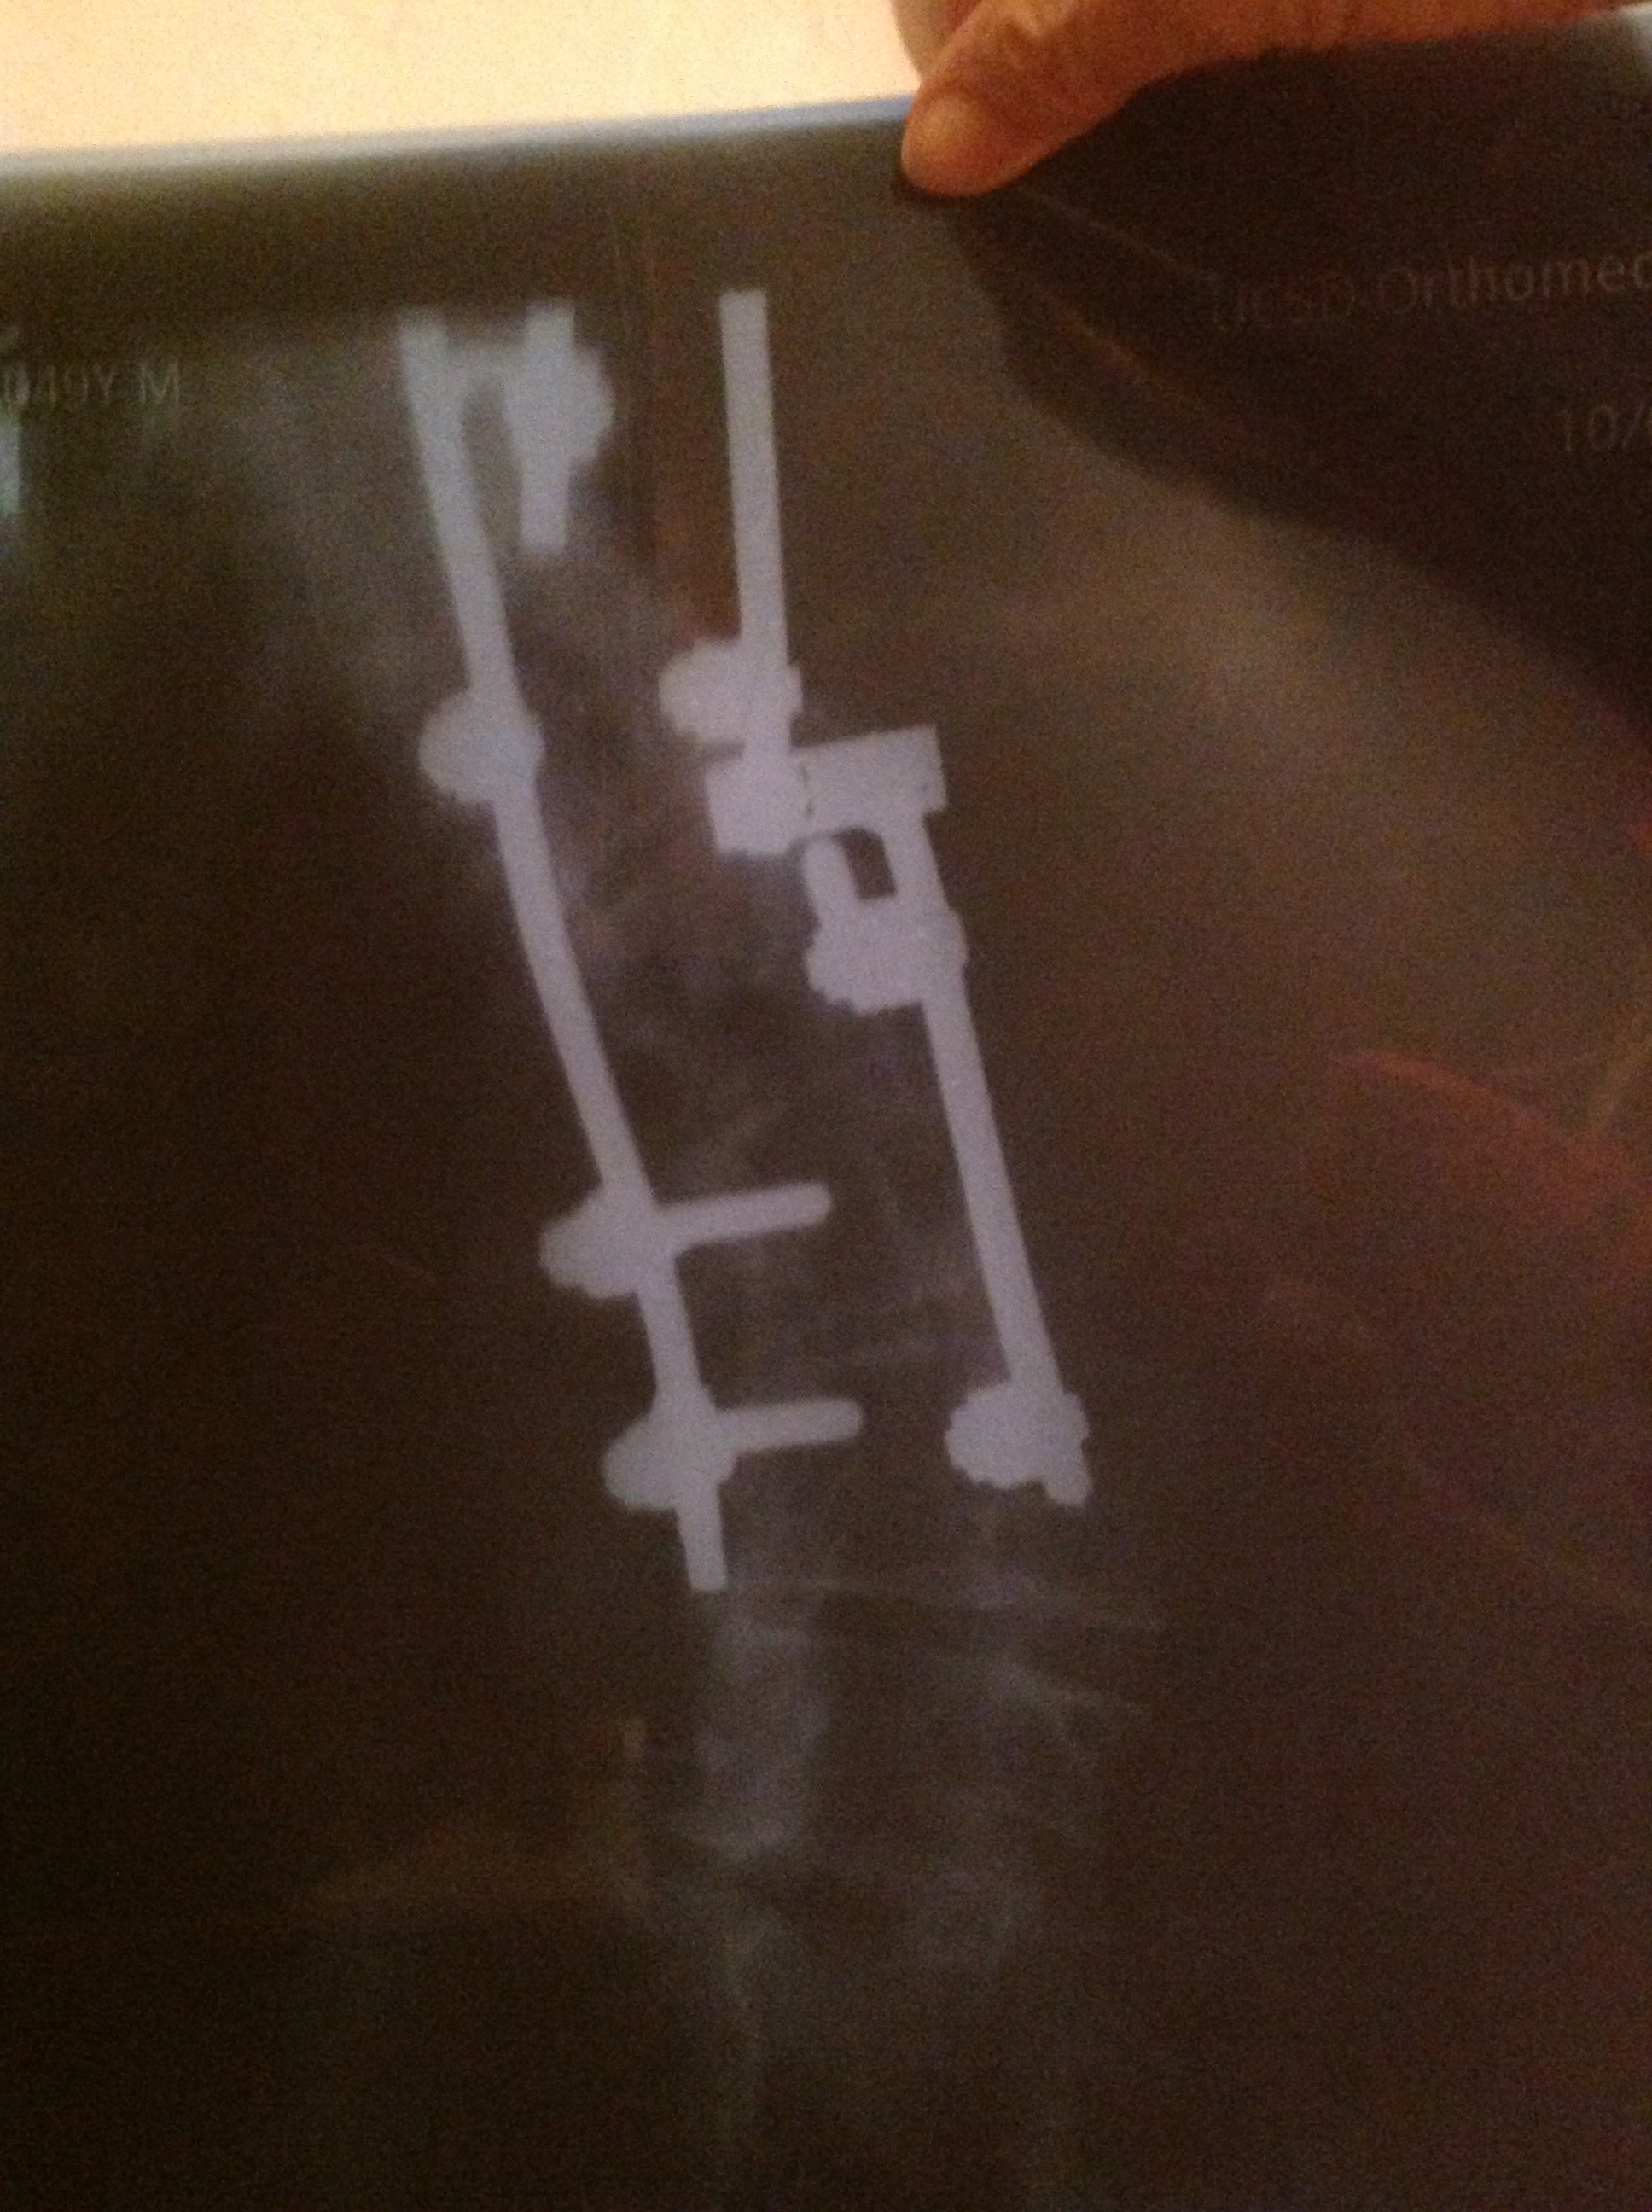

Yul Lose Posted February 1 Posted February 1 Best of luck to you. Times and procedures have changed a lot since my first 12 vertebrae were done in 1979 and 21 vertebrae, including the first 12 were fused and instrumented in 1992. I was in a body cast in 1979 for 4 months and then a back brace for 18 months after that. In 1992 I had so many complications that they put me in a medically induced coma for 2 months. They cleaned out the old fusions and discs and the other 9 discs and were going to go in the next day and do the fusions and install the hardware but I started having breathing issues and they couldn’t go back in to finish up for 5 months. So I laid in bed in a kydex jacket trying to get strong enough for them to finish. I was tube fed for nearly 3 months and had to learn how to talk, swallow and walk again. Both of the latter procedures were anterior and posterior approaches so they opened me up from tail bone to neck and across my abdomen both times. Recovery took many months. A lady that I shoot with just had 11 vertebrae done and her recovery was much faster. My surgeon told me that between my side to side and front to back curvature (scoliosis) I had 94 degree curvature, he said it was the worst he'd ever attempted to repair. Listen to and follow all of the advice that your surgeon and therapists give you, you’ll be glad you did. My X-rays. 1 2 Quote

Texas Maverick Posted February 1 Author Posted February 1 1 hour ago, Yul Lose said: Best of luck to you. Times and procedures have changed a lot since my first 12 vertebrae were done in 1979 and 21 vertebrae, including the first 12 were fused and instrumented in 1992. I was in a body cast in 1979 for 4 months and then a back brace for 18 months after that. In 1992 I had so many complications that they put me in a medically induced coma for 2 months. They cleaned out the old fusions and discs and the other 9 discs and were going to go in the next day and do the fusions and install the hardware but I started having breathing issues and they couldn’t go back in to finish up for 5 months. So I laid in bed in a kydex jacket trying to get strong enough for them to finish. I was tube fed for nearly 3 months and had to learn how to talk, swallow and walk again. Both of the latter procedures were anterior and posterior approaches so they opened me up from tail bone to neck and across my abdomen both times. Recovery took many months. A lady that I shoot with just had 11 vertebrae done and her recovery was much faster. My surgeon told me that between my side to side and front to back curvature (scoliosis) I had 94 degree curvature, he said it was the worst he'd ever attempted to repair. Listen to and follow all of the advice that your surgeon and therapists give you, you’ll be glad you did. My X-rays. All I can say is wow, glad it has all worked out for you. TM 1 Quote